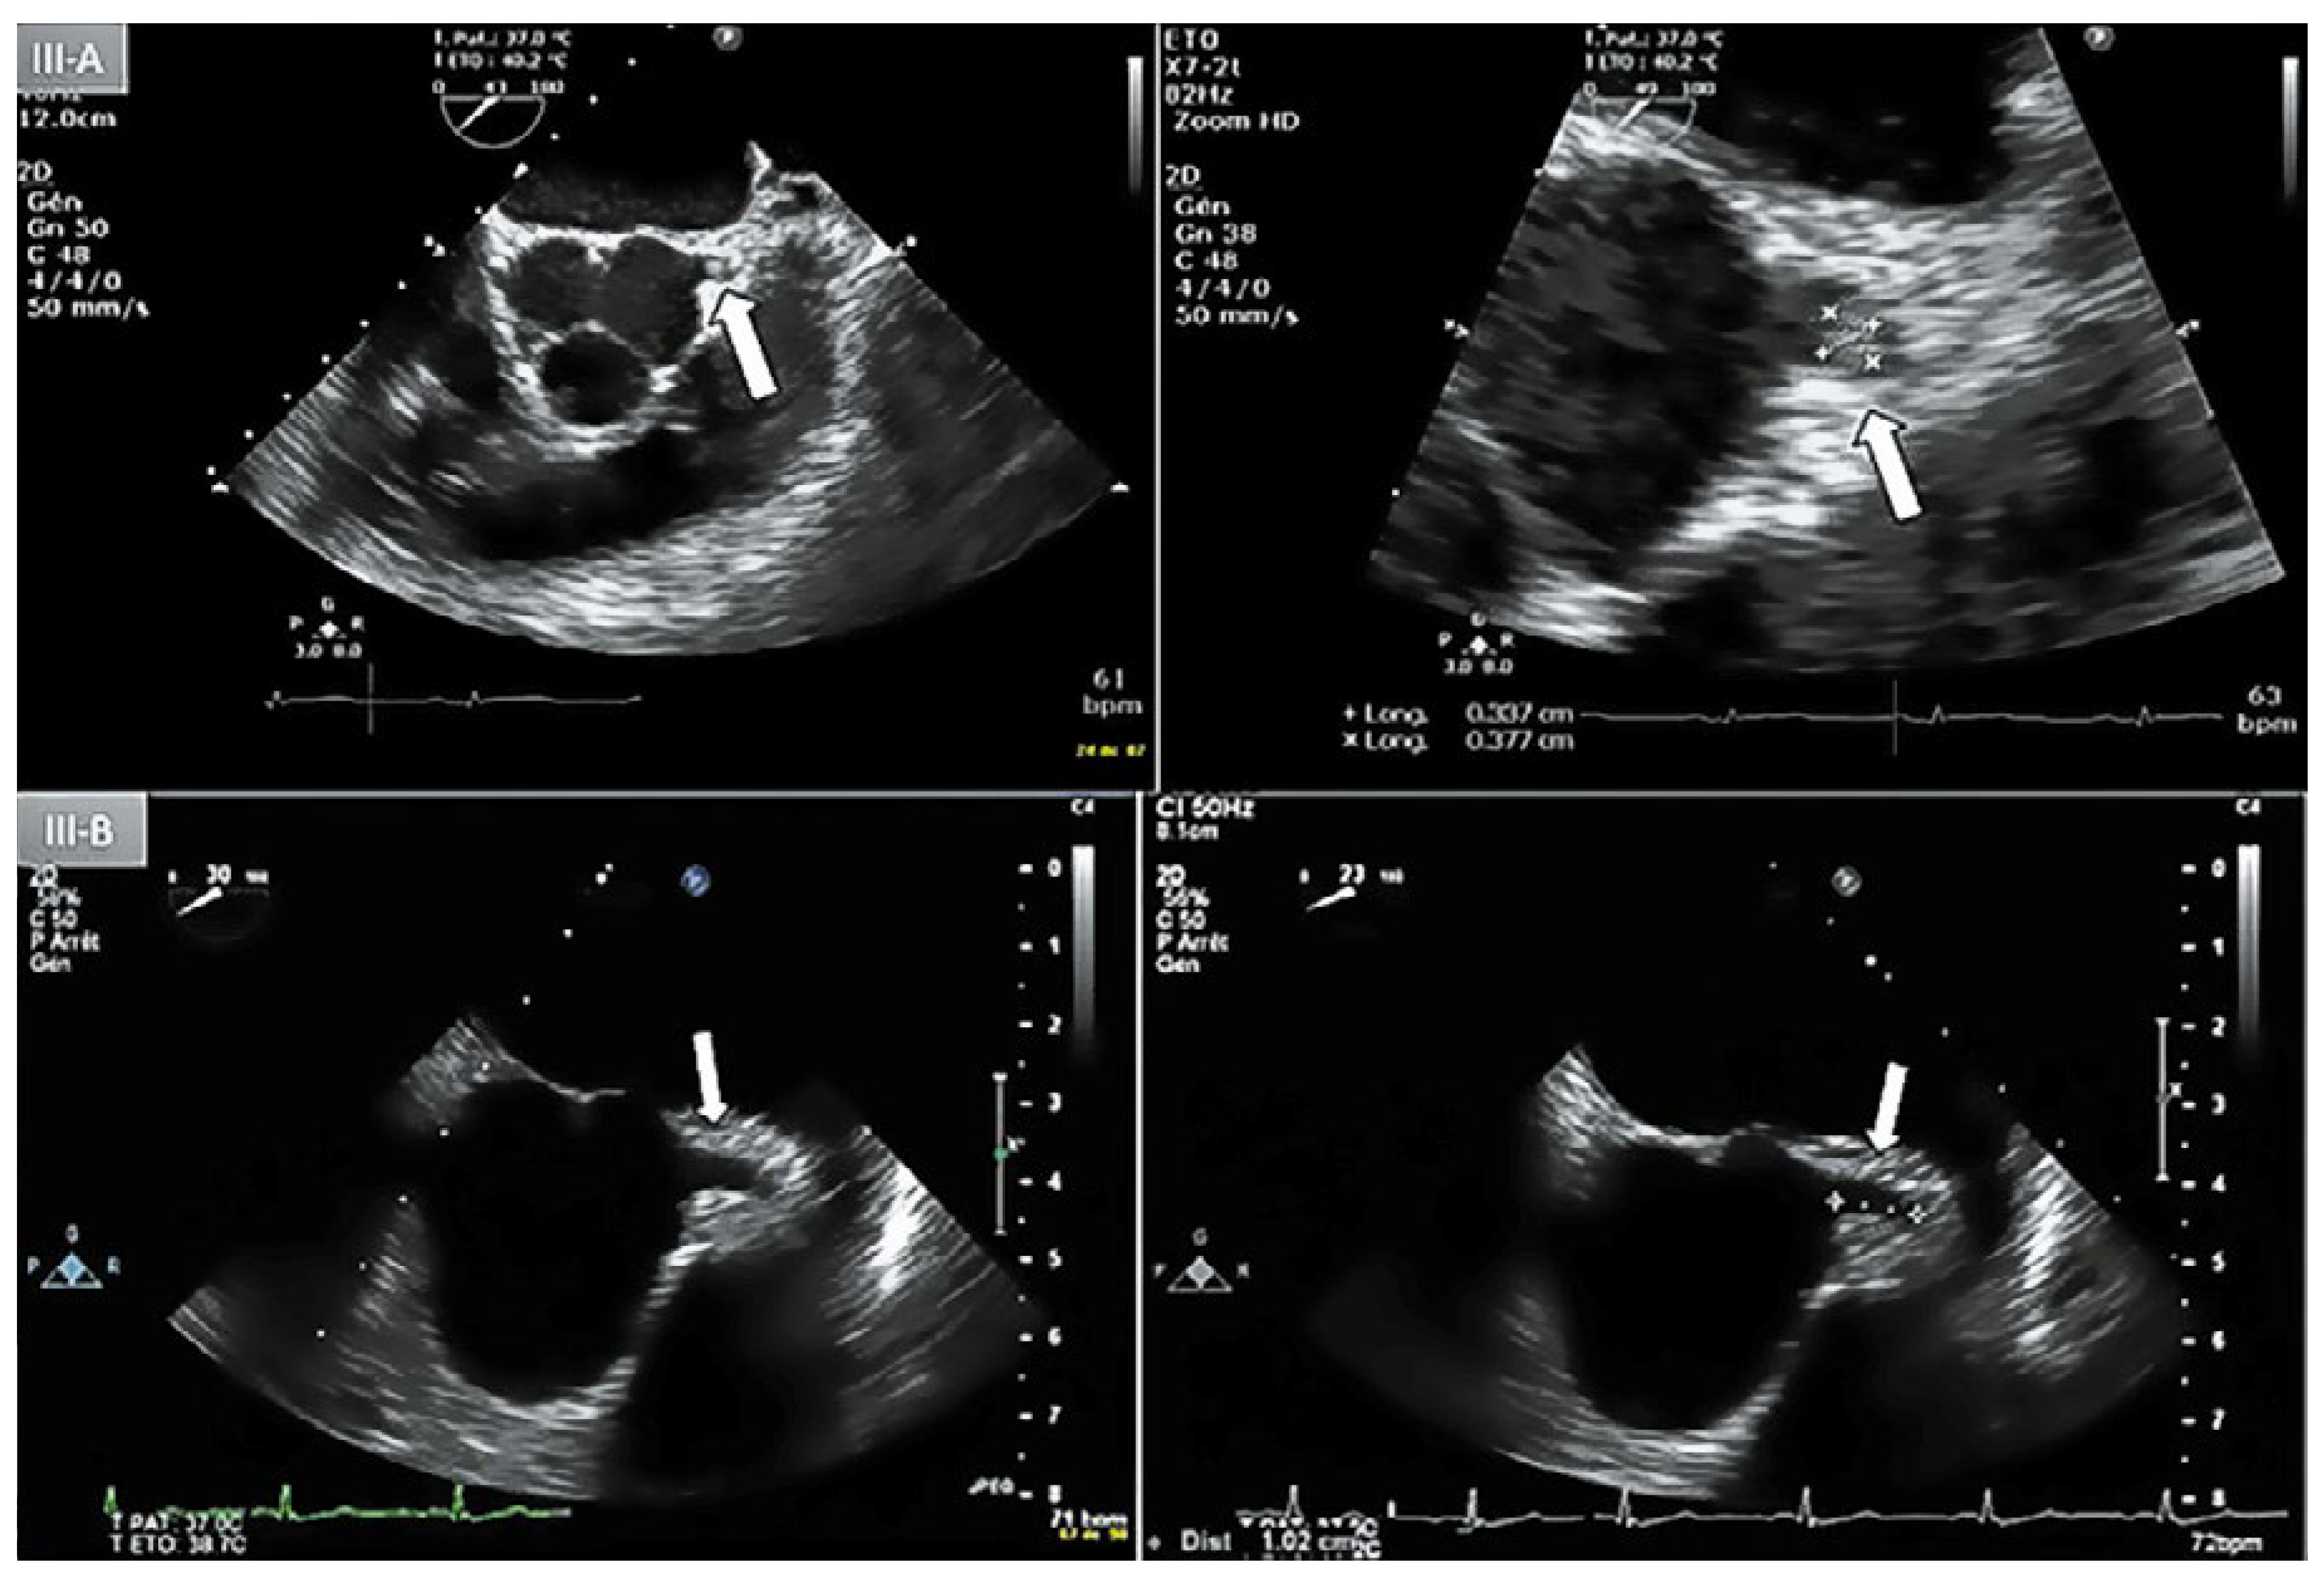

Figure 3.

A: Day-1 transoesophageal echocardiography (TEE) with short axis view showing an lntracoronary mass (3 x 3.5 mm) protruding lnto the lumen of the left main coronary artery (LMCA) (arrow). B: Day-5 repeat TEE, short axis view, absence of coronary mass in the proximal LMCA.